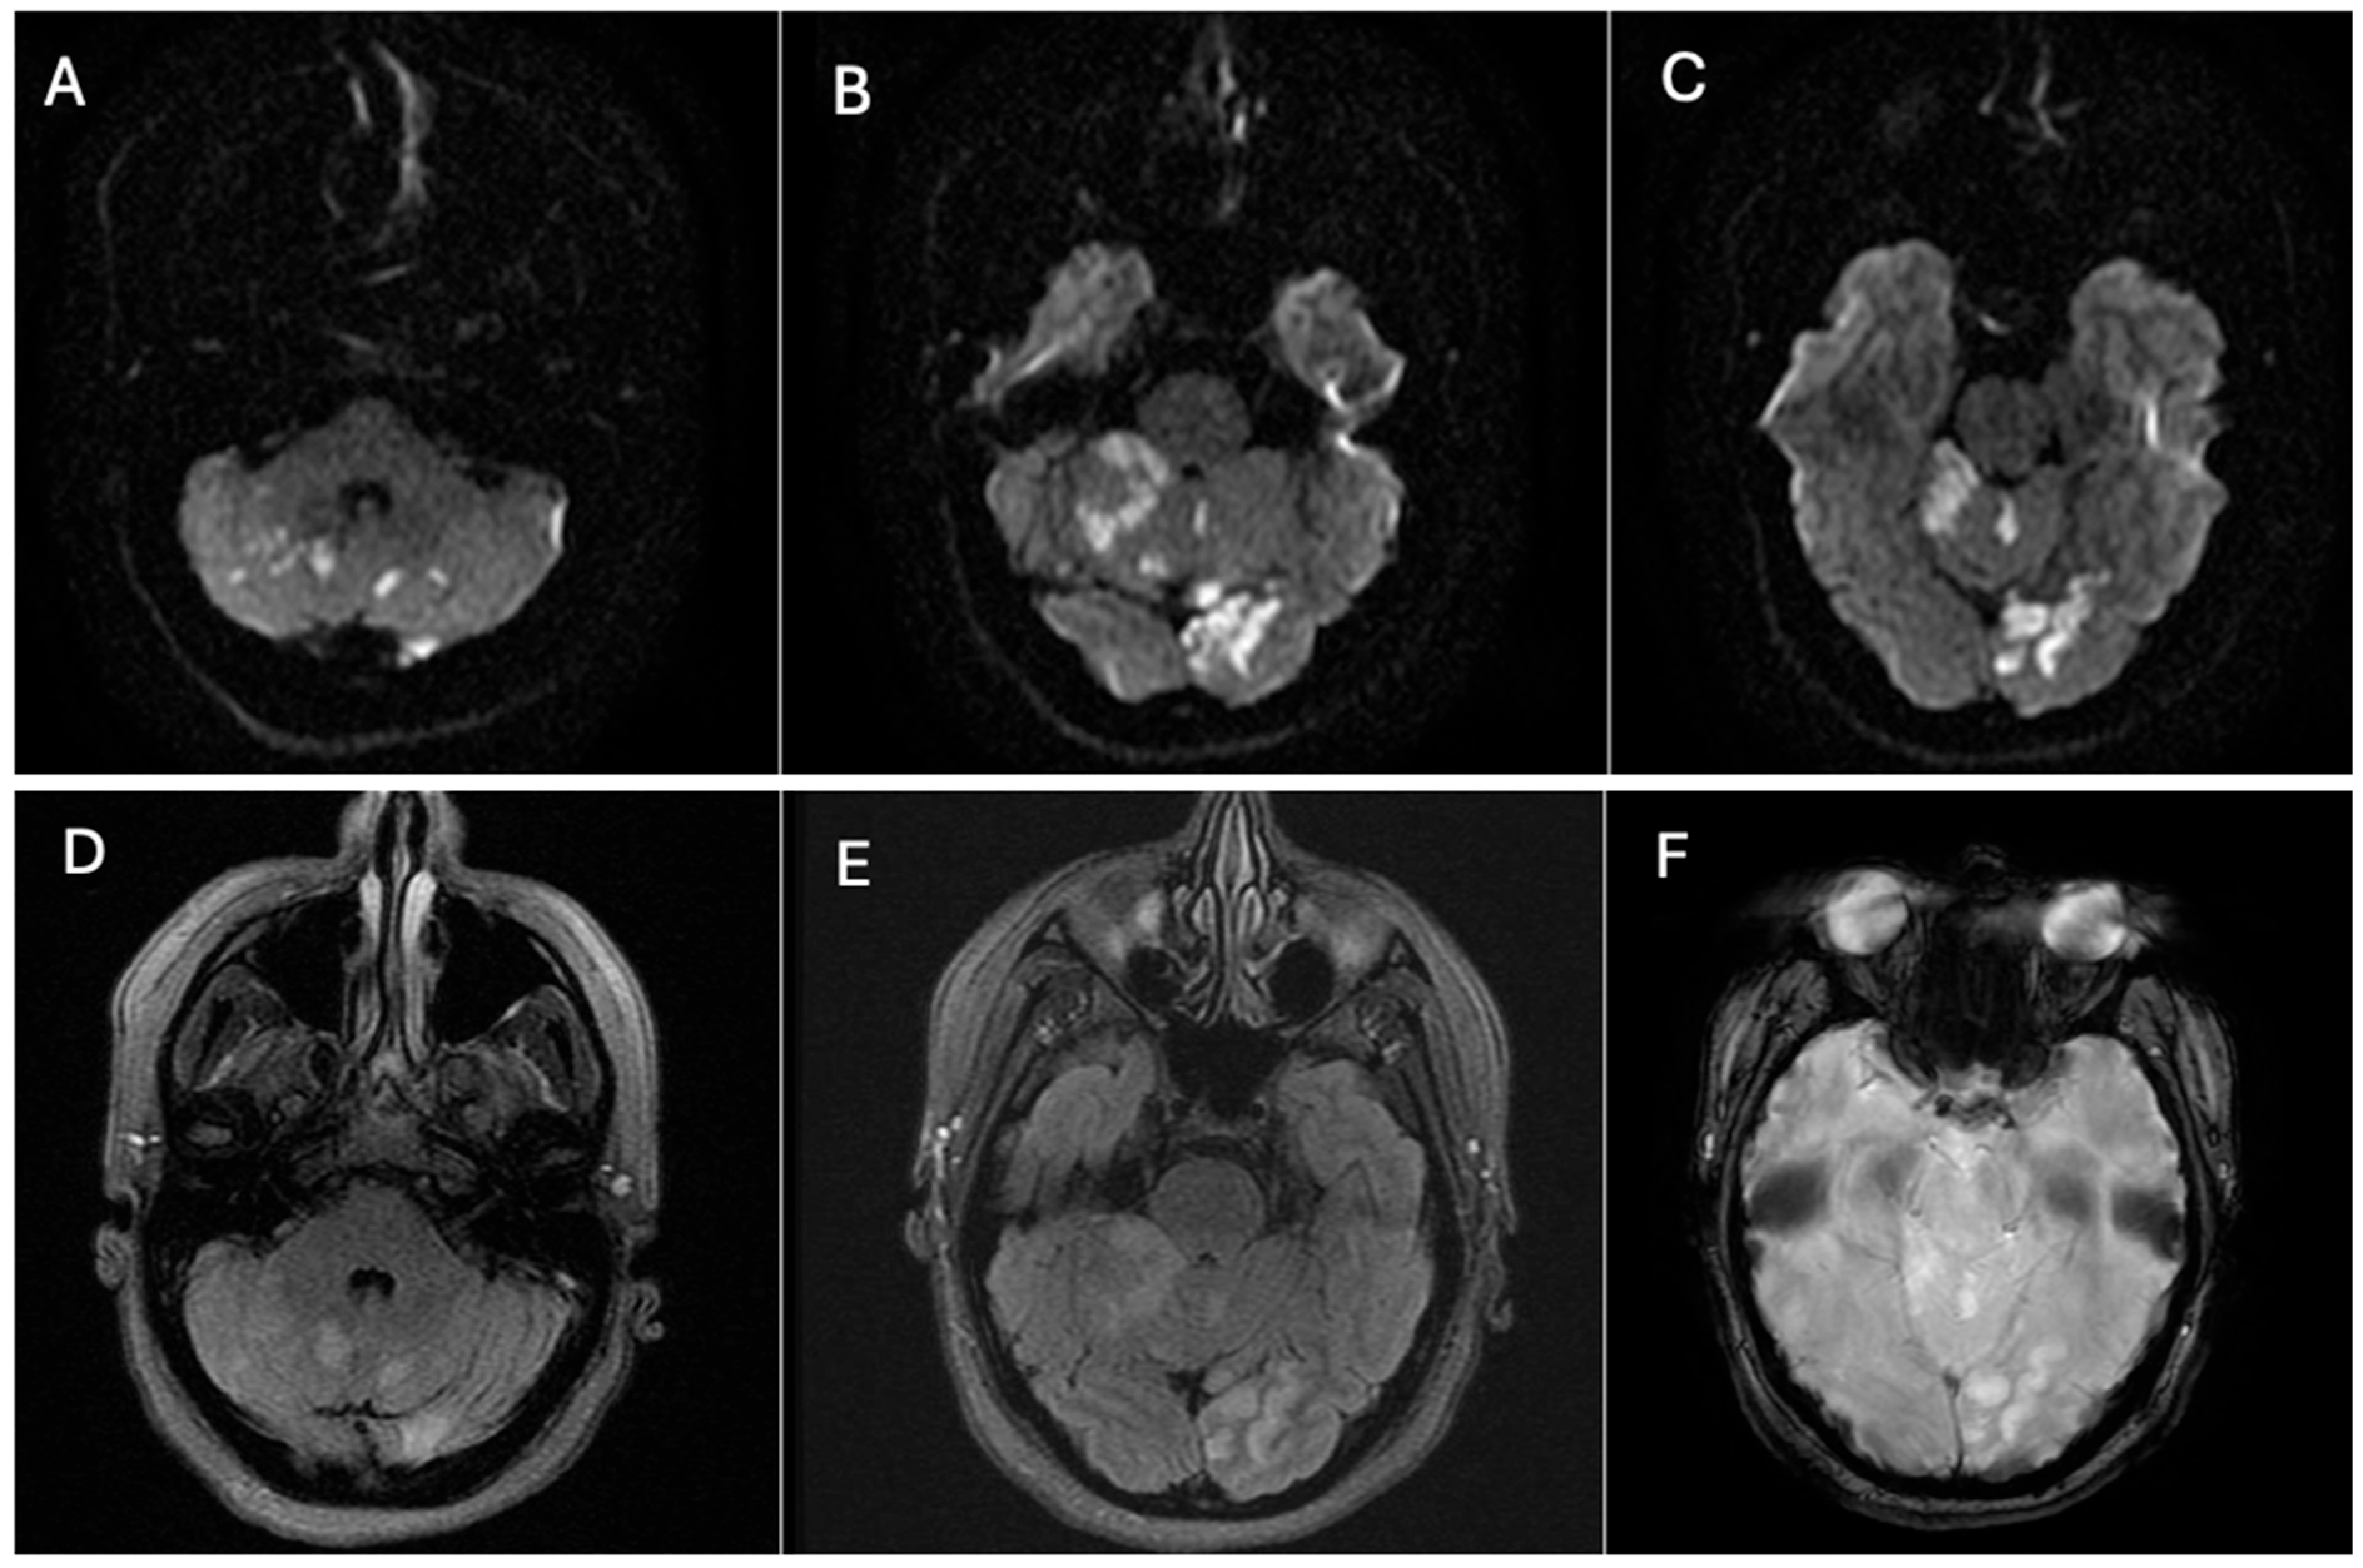

The case was urgently discussed in a multidisciplinary neurovascular team meeting comprising radiologists, interventional neurosurgeons, and neurologists. After a detailed discussion with the patient regarding the risks and benefits of available therapies, it was decided, considering the time of evolution, the patient’s age, and the aneurysm’s characteristics, to perform a reconstructive endovascular treatment using a flow-diverting stent (Pipeline Shield) (Micro Therapeutics Inc., Irvine, CA, USA) (Figure 4), initiating dual antiplatelet therapy (clopidogrel 75 mg plus acetylsalicylic acid 100 mg starting 5 days prior to the procedure and continued for 90 days). The procedure was performed using a triaxial system: a 5 Fr Navien catheter was advanced with the aid of a 0.035 guidewire. Through this, a Phenom 27 microcatheter (Medtronic, Minneapolis, MN, USA) and a 0.014 Synchro microwire (Stryker Neurovascular, Fremont, CA, USA) were navigated across the aneurysmal sac with subtle maneuvers under continuous fluoroscopic and roadmapping guidance. The distal tip of the microcatheter was successfully positioned in the left V3 segment. After systemic intravenous heparinization, the microwire was withdrawn, and a single Pipeline Shield flow-diverting and artery-remodeling stent (4.5 × 35 mm) was advanced and deployed, achieving a healthy-to-healthy proximal artery reconstruction and completely covering the aneurysm neck, which initiated its occlusion process. Control angiograms demonstrated adequate stent apposition, maintained parent vessel patency, and no periprocedural complications. Femoral access was closed with an 8 Fr Angio-Seal device (Terumo Medical Corporation, Somerset, NJ, USA). Post-procedural imaging follow-up with digital subtraction angiography (DSA) confirmed stent positioning and vessel patency.

Figure 4. Post-procedural digital subtraction angiography (DSA) and three-dimensional reconstruction images following reconstructive endovascular treatment with a flow-diverting stent (Pipeline Shield). The stent is clearly visualized along the course of the left vertebral artery and is indicated by the red arrow. Source: patient’s medical record, published with prior authorization.